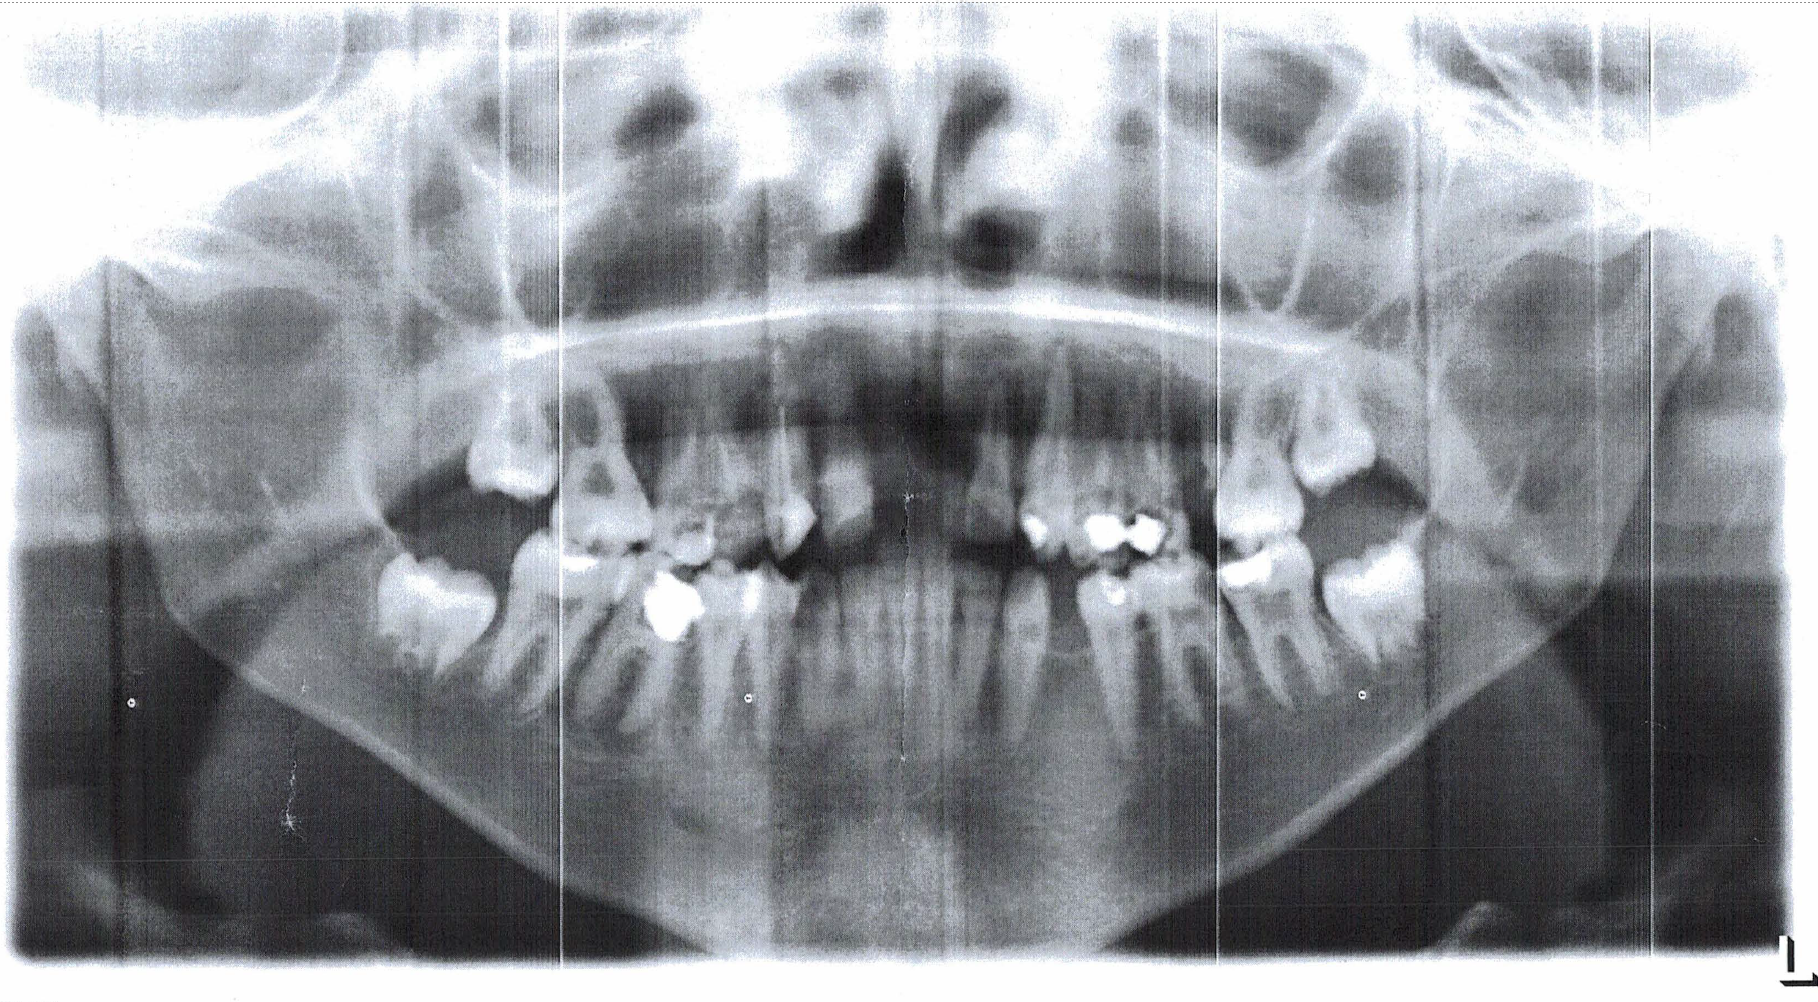

When she was finally taken to St. Francis Hospital, Naggalama, doctors reported that she had no healthy tooth left in her mouth. They could only save seven of them and recommended replacing the rest with artificial teeth, an expense far beyond her family’s means. Her younger brother Nicolas also suffers from untreated asthma. He has lived with untreated lung complications for six years.

Teddy’s story is one of endurance, love, and loss, but it also reflects the struggles of countless Ugandan families who face treatable illnesses without access to affordable care. Thanks to the generosity of CARITAS For Children donors, Teddy is receiving the life-changing dental treatment she needs, to restore all her teeth for her 17th birthday at a fraction of what such care would cost in the United States.